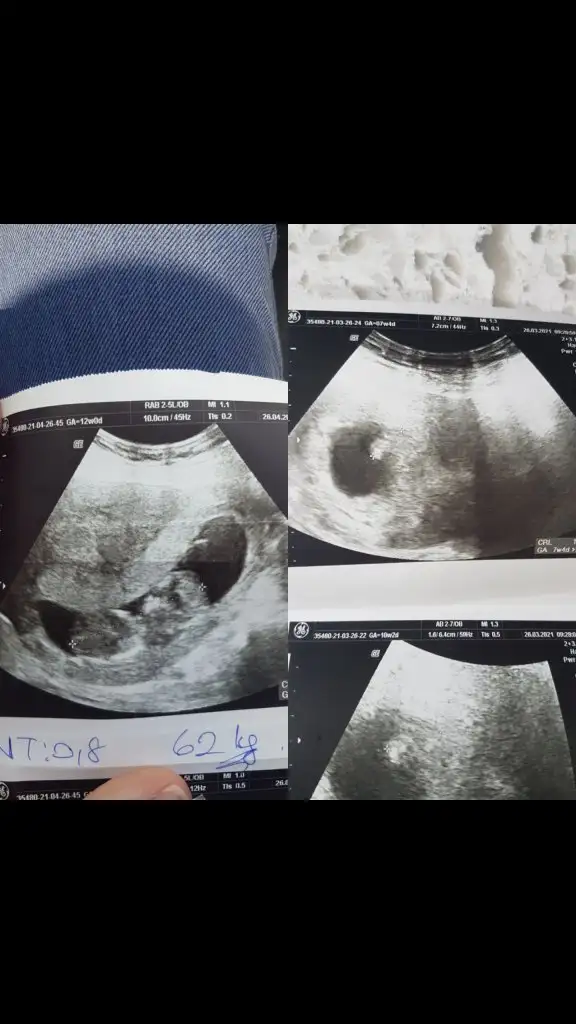

Ne güzel perşembe tekrar göreceksin o zaman sorun olmadığı için sevimdim böyle devam eder inşallahKızlar bebişimi gördüm çok şükür bir sıkıntı yokcinsiyet söylemedi perşembe birdaha çağırdı bebişin pozisyonu ense için uygun değildi malum ben burda özel hastane yok perşembe sabah birdaha geleceğim

Kızlar bebişimi gördüm çok şükür bir sıkıntı yokcinsiyet söylemedi perşembe birdaha çağırdı bebişin pozisyonu ense için uygun değildi malum ben burda özel hastane yok perşembe sabah birdaha geleceğim